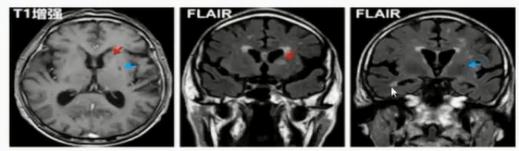

(4)脑小血管病白质高信号特征

(5)脑小血管病白纸高信号特征

(1)多发性硬化

➤ 脑和脊髓均可有病灶,多病灶,非对称性,通常有相对固定的分布模式及形态;

➤ 病灶与侧脑室垂直分布;

➤ T1WI低信号,T2WI高信号(煎蛋状、云雾状),FLAIR高信号,急性期DWI呈高信号, 增强后呈C形或开环状强化。

(影像由南京鼓楼医院提供)